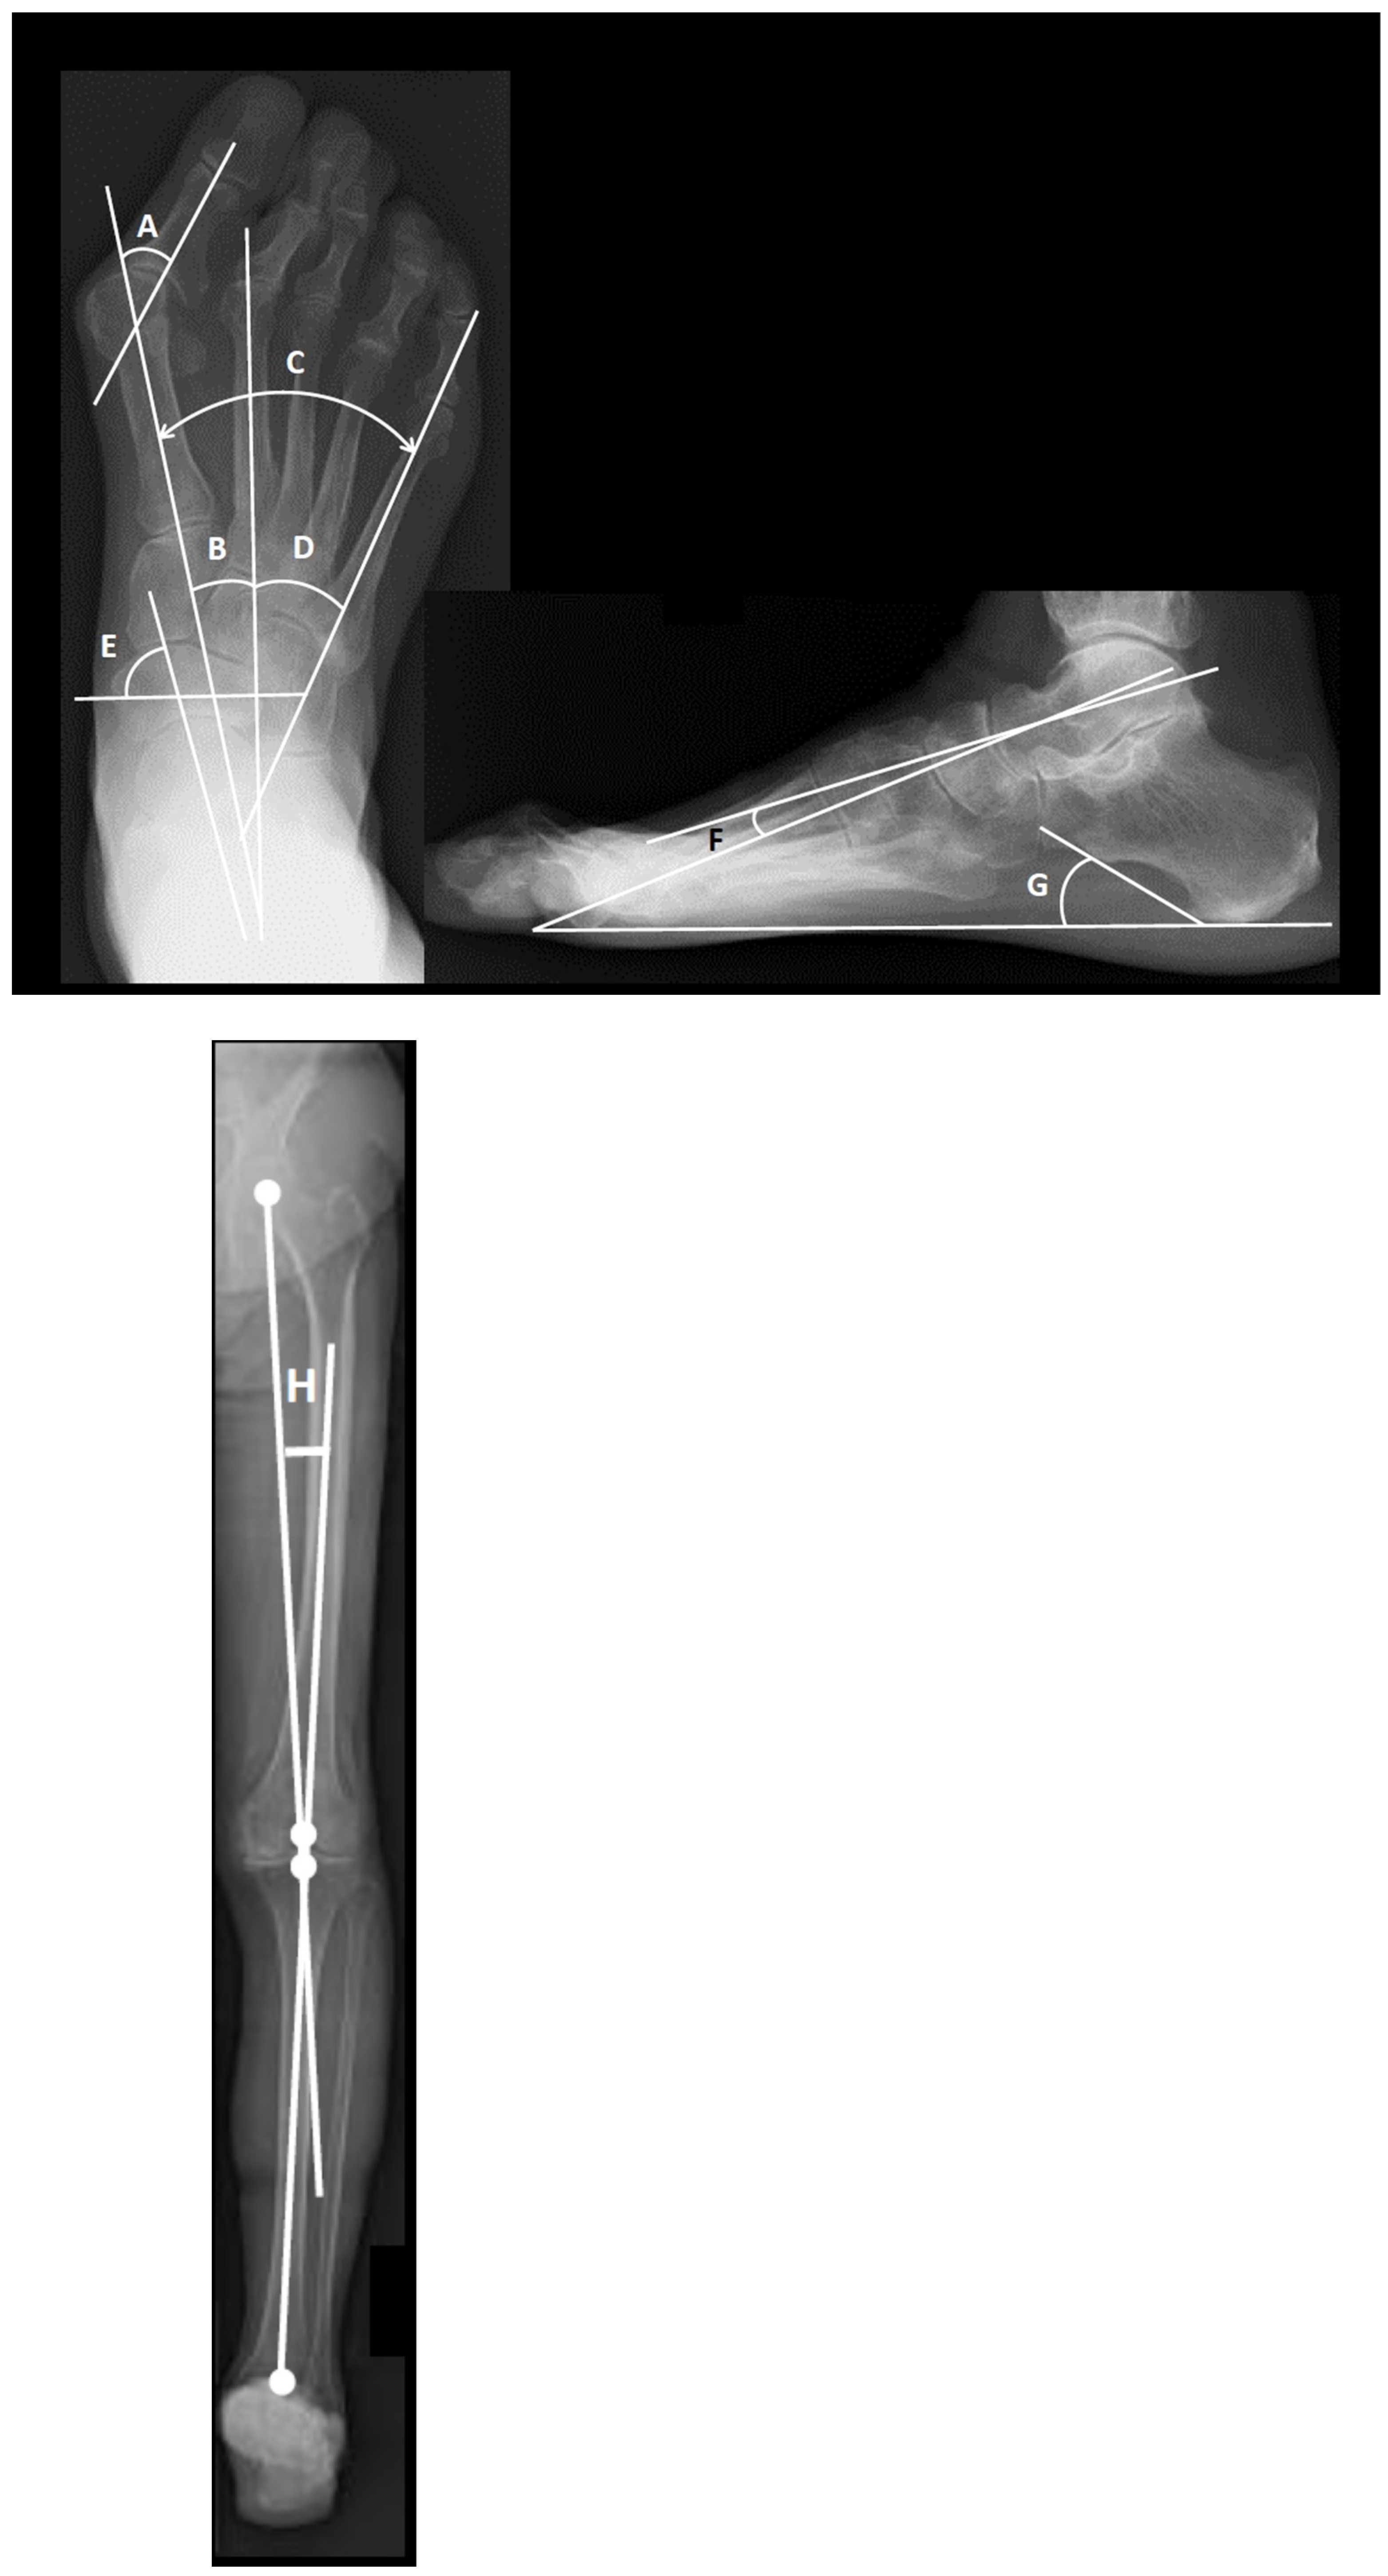

2.2. Radiographic Assessment

| HKA (hip–knee–ankle) angle (°) | 0.4 ± 5.3 (−15–8) |

| Tibiocalcaneal angle (°) | 6.3 ± 5.6 (−10–28) |

| Pronated foot index (°) | 73.4 ± 12.4 (40–101) |

| Talo-1st metatarsal angle (°) | 14.0 ± 11.5 (−17–51) |

| Calcaneal pitch angle (°) | 15.4 ± 6.4 (−2–31) |

| Intermetatarsal angle between 1st and 2nd metatarsal bones (°) | 11.9 ± 5.0 (2–30) |

| Intermetatarsal angle between 1st and 5th metatarsal bones (°) | 32.2 ± 6.8 (13–47) |

| Intermetatarsal angle between 2nd and 5th metatarsal bones (°) | 20.3 ± 5.7 (7–33) |

| Hallux valgus angle (°) | 30.7 ± 18.2 (−4–66) |